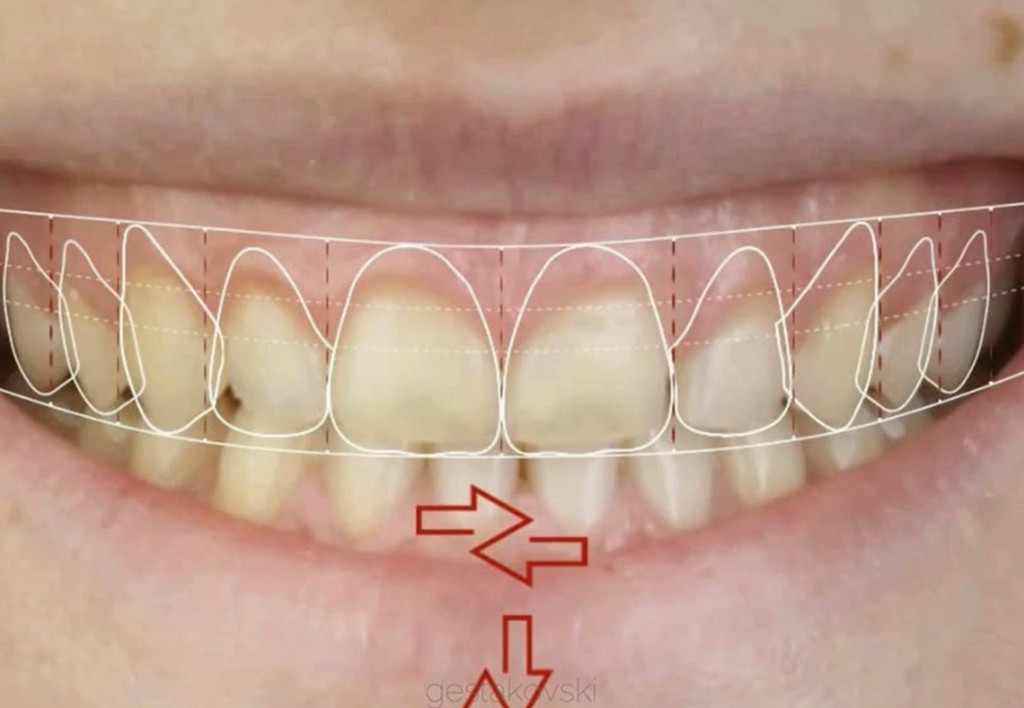

► Smile Design (analogico e digitale - DSD)

► Mock-up e pre-visualizzazione

► Pianificazione analogica e digitale: sviluppa un piano di trattamento accurato e personalizzato.

Galleria fotografica